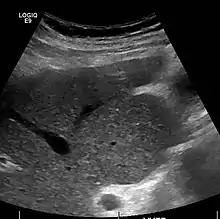

Ultrasound is routinely used in the evaluation of cirrhosis.[34] It may show a small and shrunken liver in advanced disease. On ultrasound, there is increased echogenicity with irregular appearing areas.[51] Other suggestive findings are an enlarged caudate lobe, widening of the fissures and enlargement of the spleen.[52] An enlarged spleen, which normally measures less than 11–12 cm (4.3–4.7 in) in adults, may suggest underlying portal hypertension.[53] Ultrasound may also screen for hepatocellular carcinoma and portal hypertension.[34] This is done by assessing flow in the hepatic vein.[54] An increased portal vein pulsatility may be seen. However, this may be a sign of elevated right atrial pressure.[55] Portal vein pulsatility are usually measured by a pulsatility indices (PI).[54] A number above a certain values indicates cirrhosis (see table below).